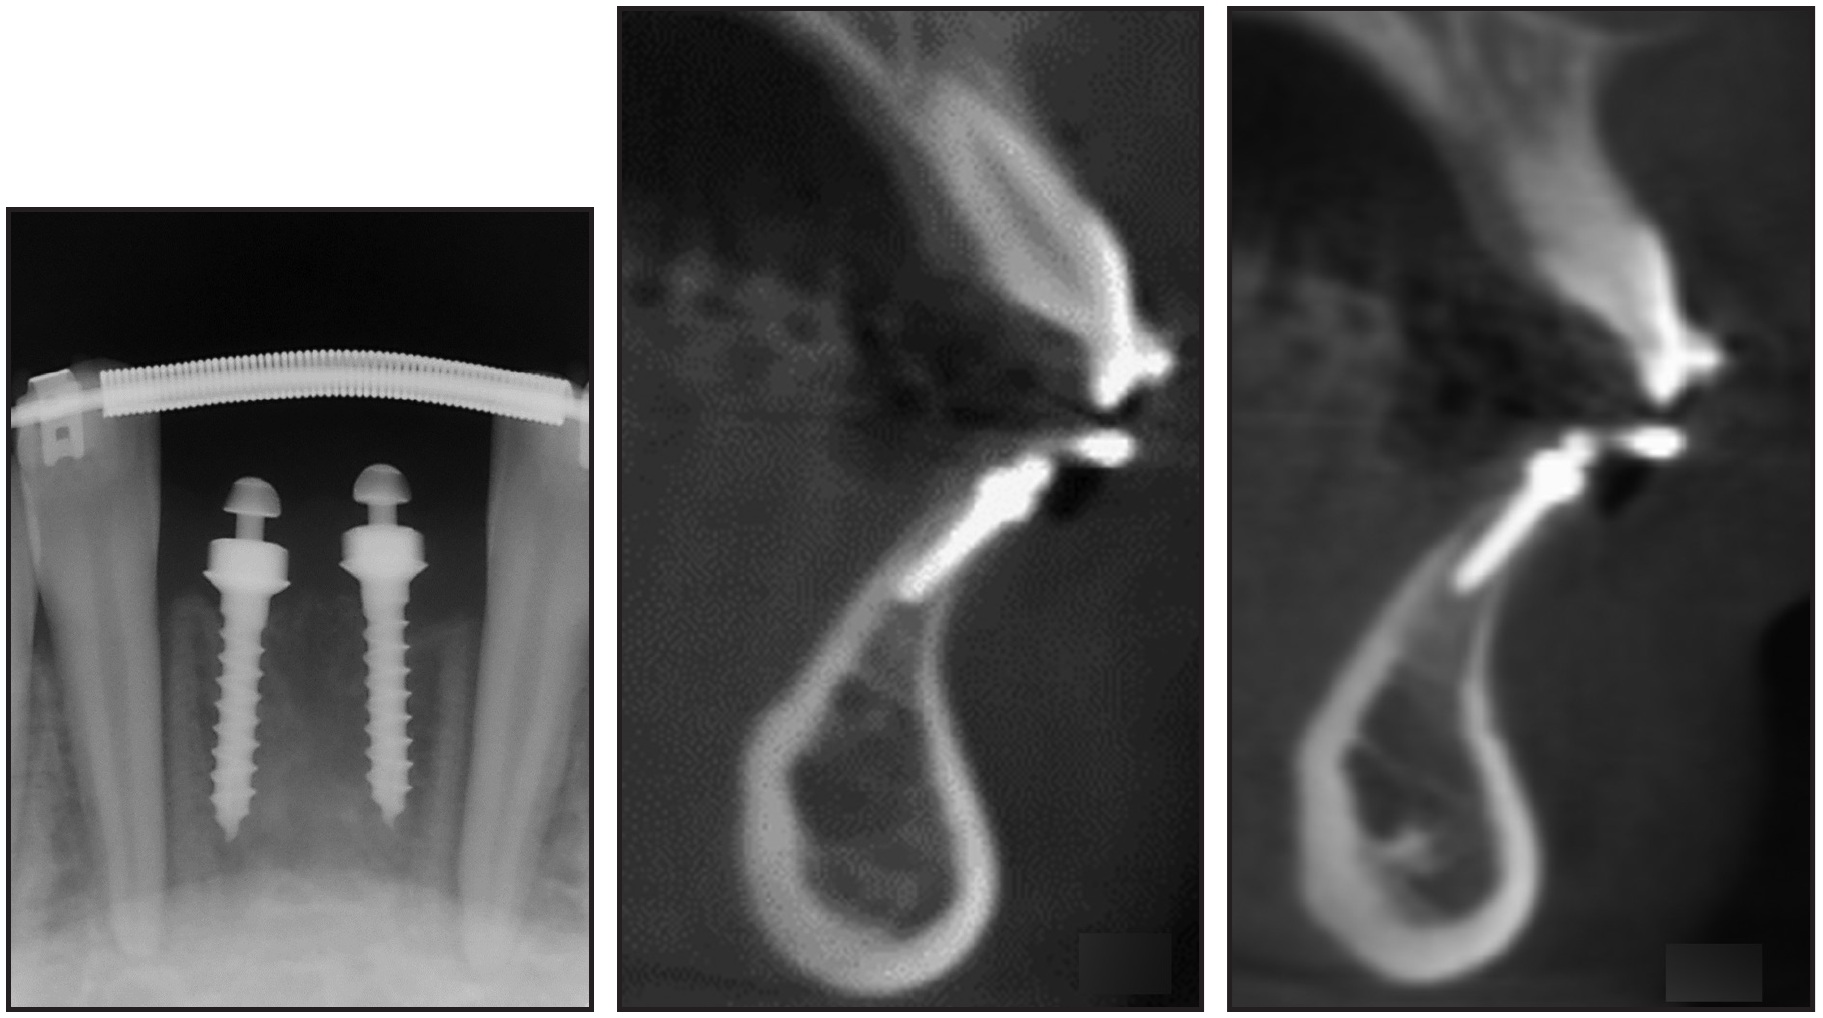

Fig. 2 Two 1.8mm × 8.5mm C-implants used for total protraction of upper dentition to correct anterior crossbite with pushing technique.

The C-implant directly refuted the academic argument that titanium miniscrews should not be osseointegrated. The primary concern was that a screw with a small diameter (1.2-2mm) could easily be fractured. This argument might have applied to miniscrews that were used as simple anchorage for conventional orthodontic treatment. When mini-implants serve not only as skeletal anchorage but also as orthodontic appliances, however, a stronger retention force is required. For that reason, the titanium C-implant was designed with a sandblasted, large-grit, acid-etched (SLA) surface treatment to enable osseointegration as the main means of retention. The partially osseointegrated C-implant could thus serve as an alternative to the conventional large-diameter dental implant in a number of heavy-force applications (Fig. 2). The osseointegration potential of the C-implant has been proven through various animal experiments and clinical studies, and the nanostructure of the screw surface and bone attachment has been evaluated using atom-probe tomography.1,3-6